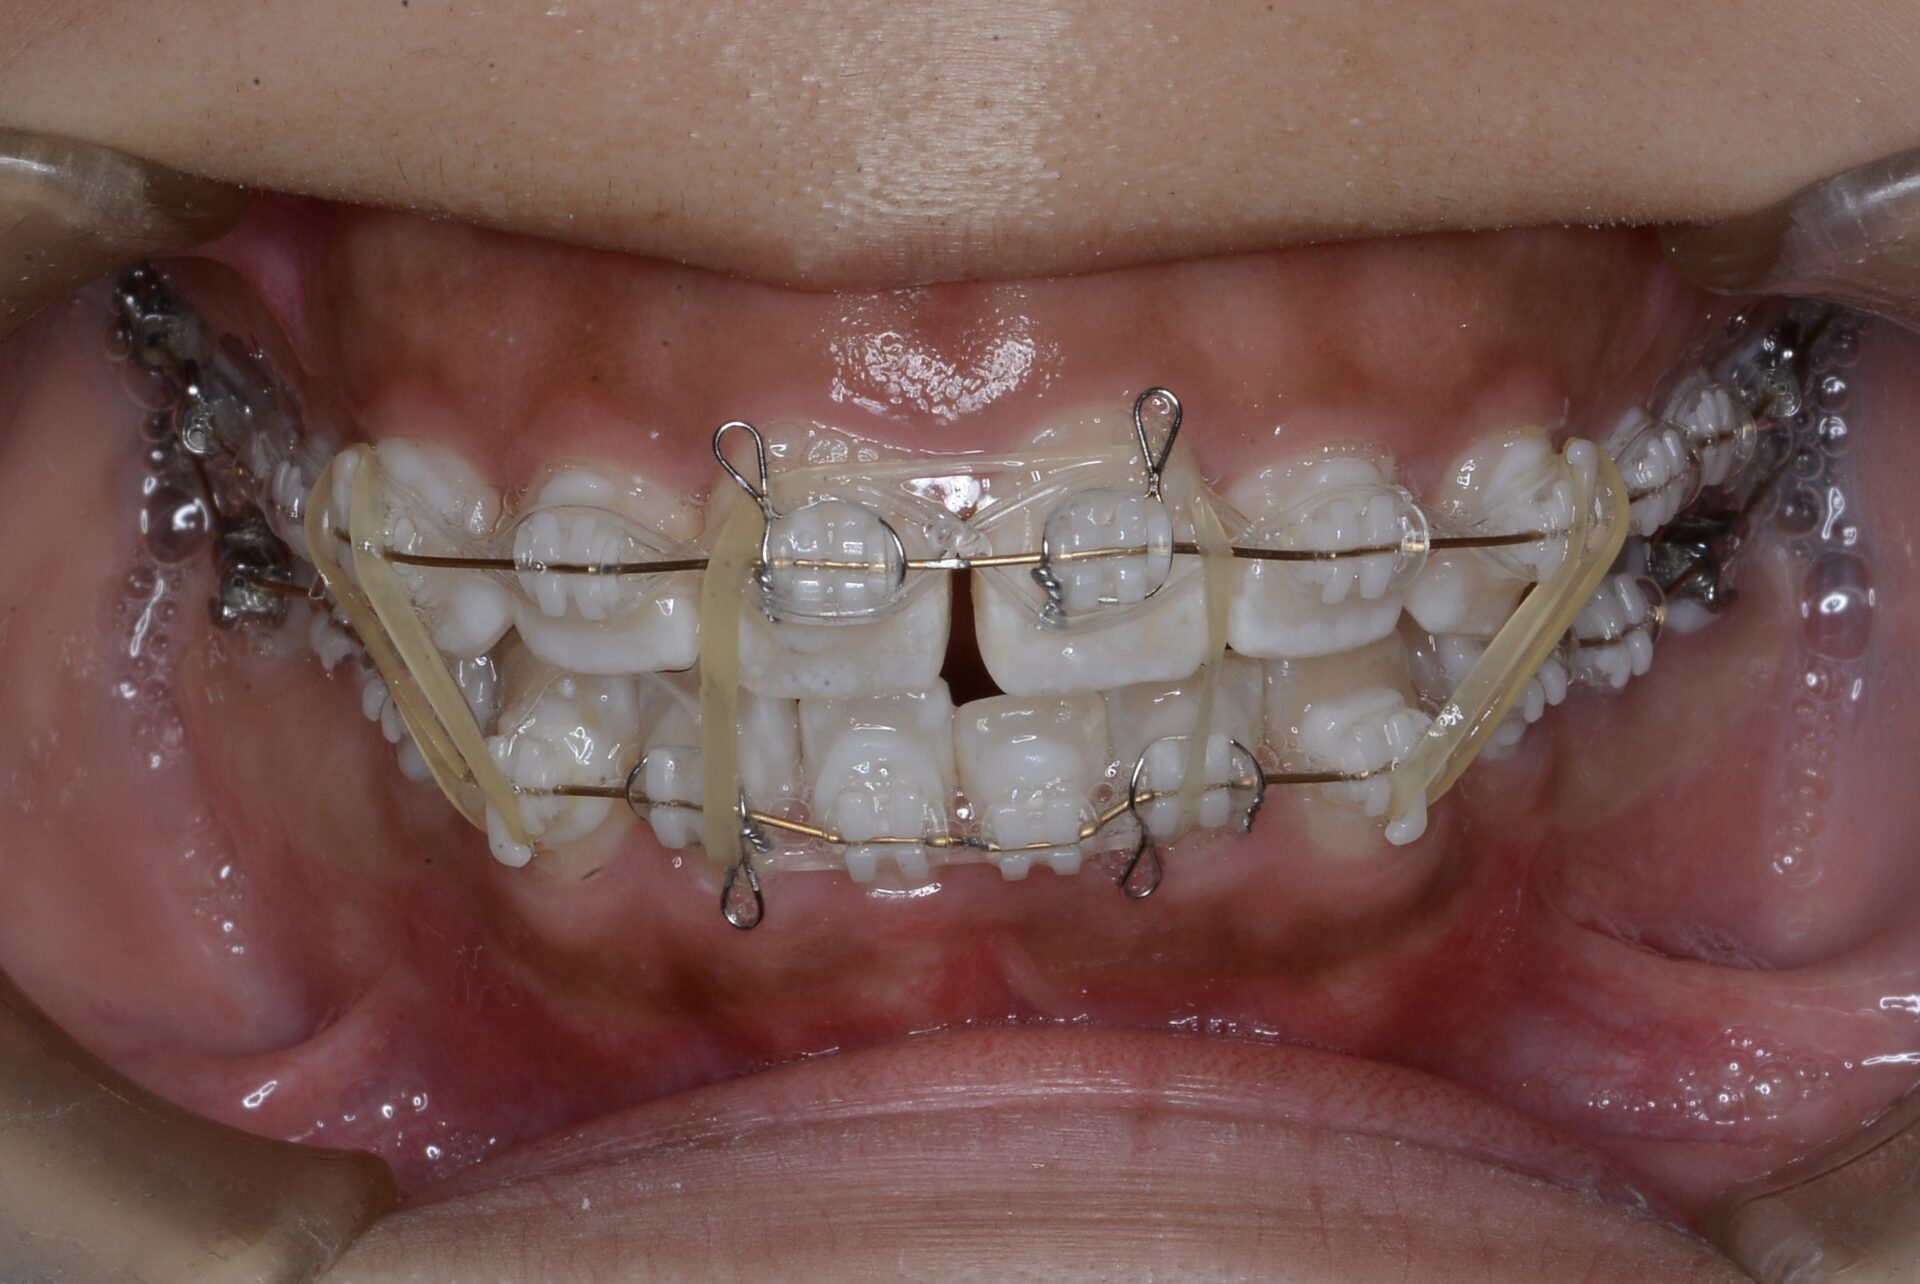

before

矯正治療スタート(22歳)

矯正治療スタート時

親知らずに押され臼歯部での噛み合わせが高くなってしまい、前歯が噛まなくなってしまっている。